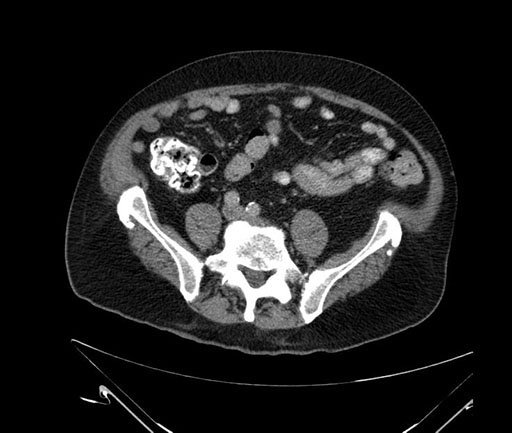

Coronal - stented